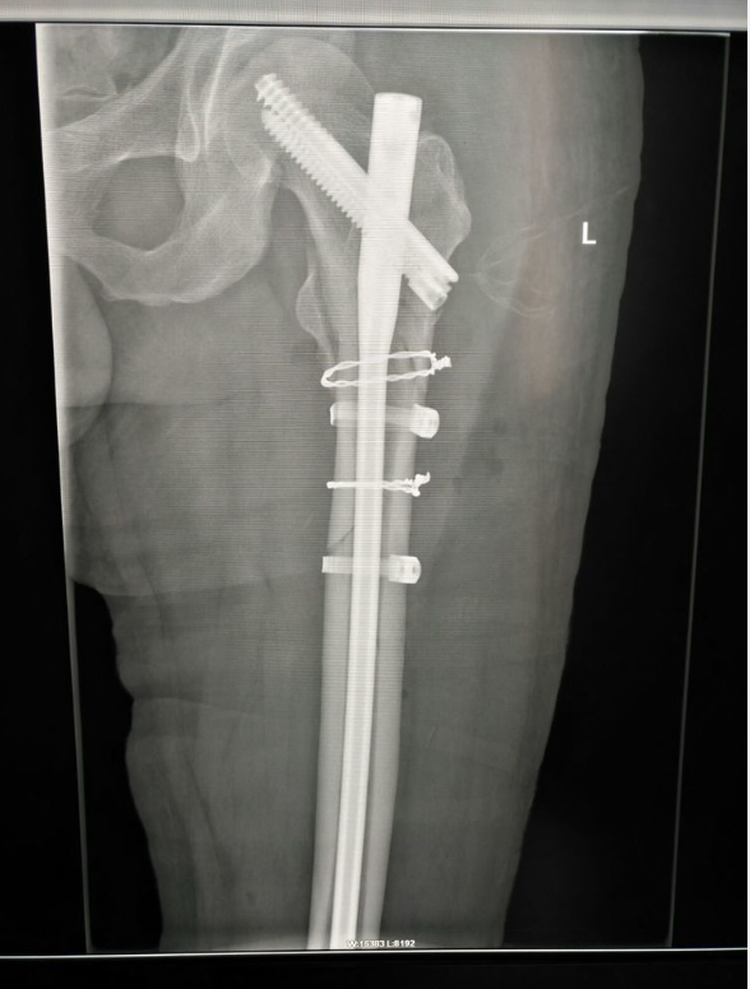

術(shù)后X線檢查